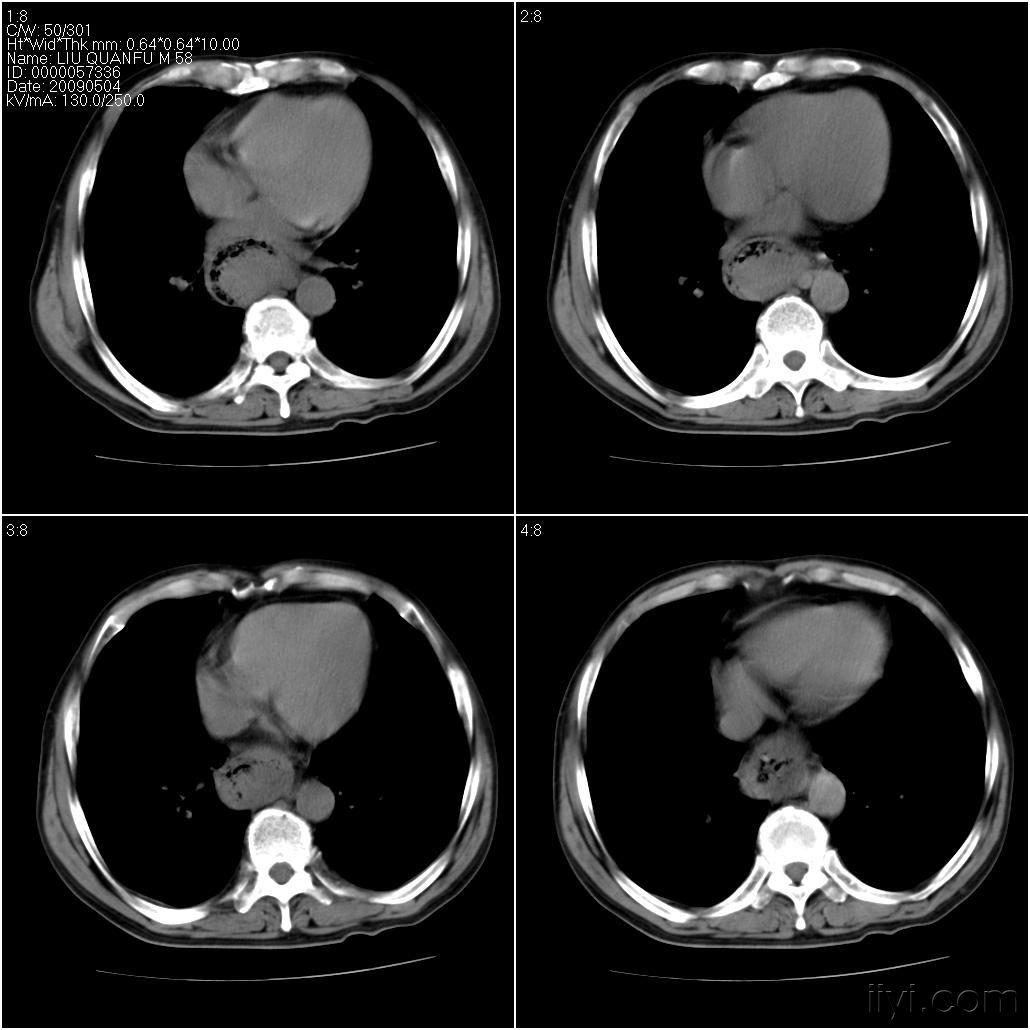

2025年中国食管癌药物行业市场规模、重点企业分析及行业发展趋势食管癌是常见的消化道肿瘤,按照不同的病理分型,可细分为鳞状细胞癌、腺癌、黏液表皮样癌等。早期食管癌患者多无明显的临床症状,部分患者会在进食时感觉有哽噎感和异物感,而随着病情的发展,中晚期食管癌患者会出现进行性吞咽困难,持续性胸骨后疼痛,呕血或便血,且伴随消瘦等...

寿命短的男性吃饭常有5个表现,全无说明身体硬朗!一名62岁的老年男性患者,出现进行性吞咽困难已经整整半年了,而短短半年的时间,患者的体重也从140斤下降到120斤,为了查明病因,患者来到医院,通过胃镜检查,很快明确为食管癌。 糟糕的是,由于拖得时间太长,确诊的时候食管癌已经发生了远处转移,失去了手术根治的机会。 另外一名...

食道癌一查多是晚期,5大症状早有警示,很多人却未察觉62 岁的胡先生因进行性吞咽困难前往医院就诊,经检查,医生发现致使胡先生吞咽困难的真正原因是食道癌。 食道虽无消化食物与吸收营养的功效,但它是连接咽喉部与胃的重要器官。一旦食道里生长恶性肿瘤,直接后果便是食物难以下咽,即出现吞咽困难,想要吞咽却又无法实现。 那么,身...